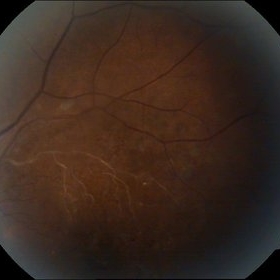

Age-Related Macular Degeneration

Sep 10 2014 by Mehul A Shah

65-year-old female presented with sudden loss of vision.

Photographer: Drashti Netralaya, Dahod

Imaging device: FF 450

Condition/keywords: age-related macular degeneration (AMD)